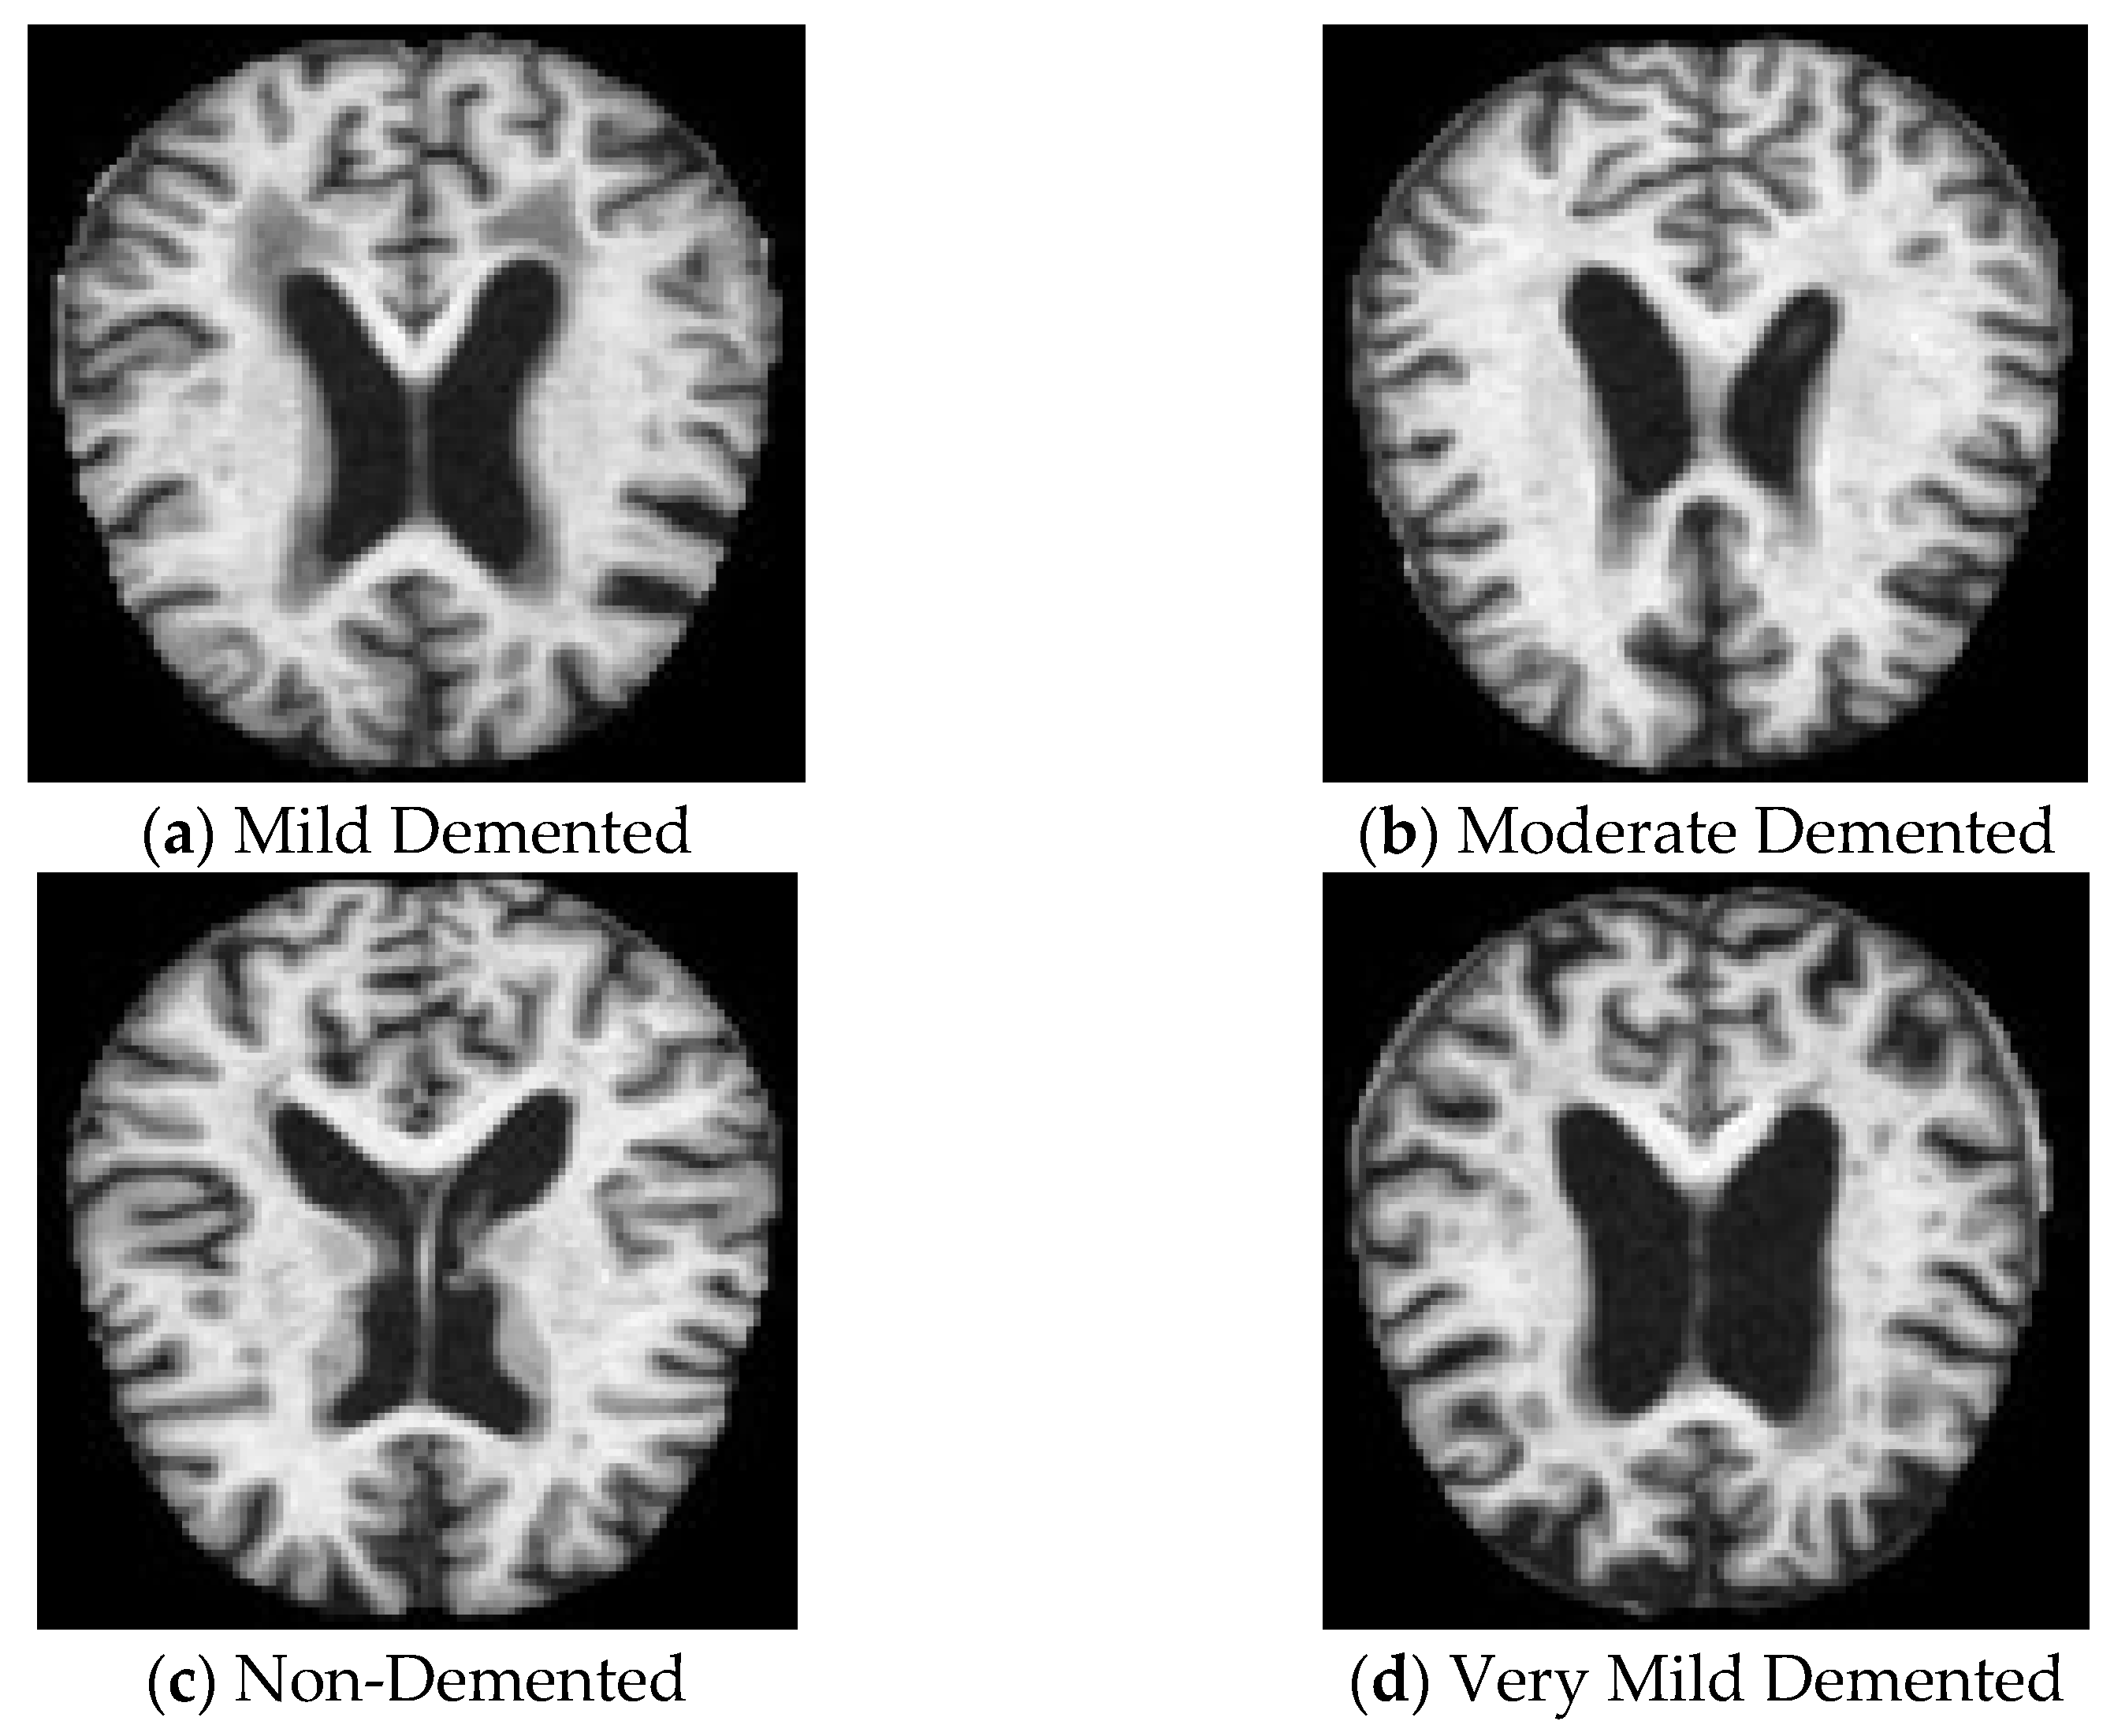

The data used for the experiment comprise the Alzheimer’s MRI dataset, obtained from Kaggle [16]. It comprises 6400 MRI scanned images of the brain, divided into four classes: class 0 (Mild Demented), class 1 (Moderate Demented), class 2 (Non-Demented), and class 3 (Very Mild Demented) of 128 × 128 pixels each. Figure 1 shows sample images from each class of the dataset. As part of the preprocessing steps, pixel values were normalized to a range of [0, 1], a technique that aids in the faster convergence of DL models by scaling the inputs. Following normalization, the dataset was split into three subsets, allocating 80% for training, 10% for testing, and 10% for validation. The training dataset contains 5120 images; the testing and validation datasets contain 640 images each.

Figure 1.

Dataset images from each class.